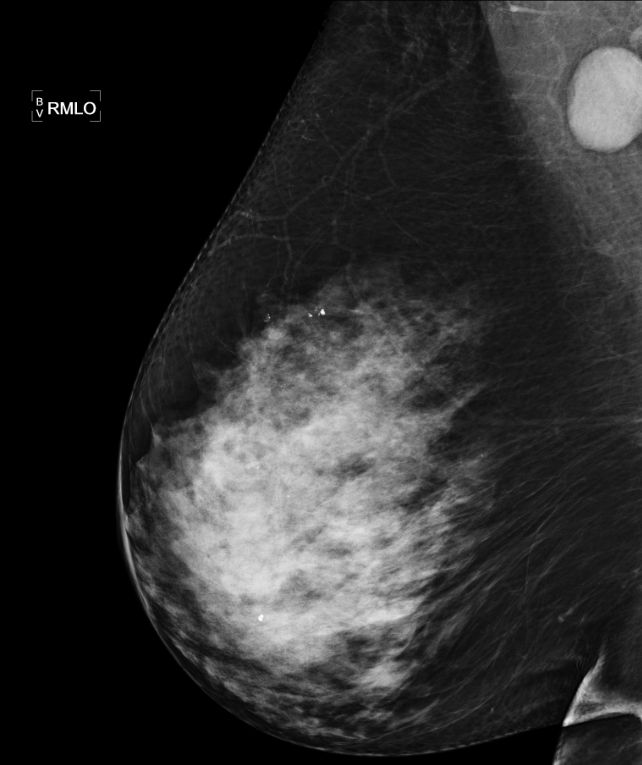

Mamma und axilläre LK |

71-jährige Frau mit diffuser Schwellung und

Rötung der rechten Brust.![]() |

großer axillärer Lymphknoten erkennbar.![]() |